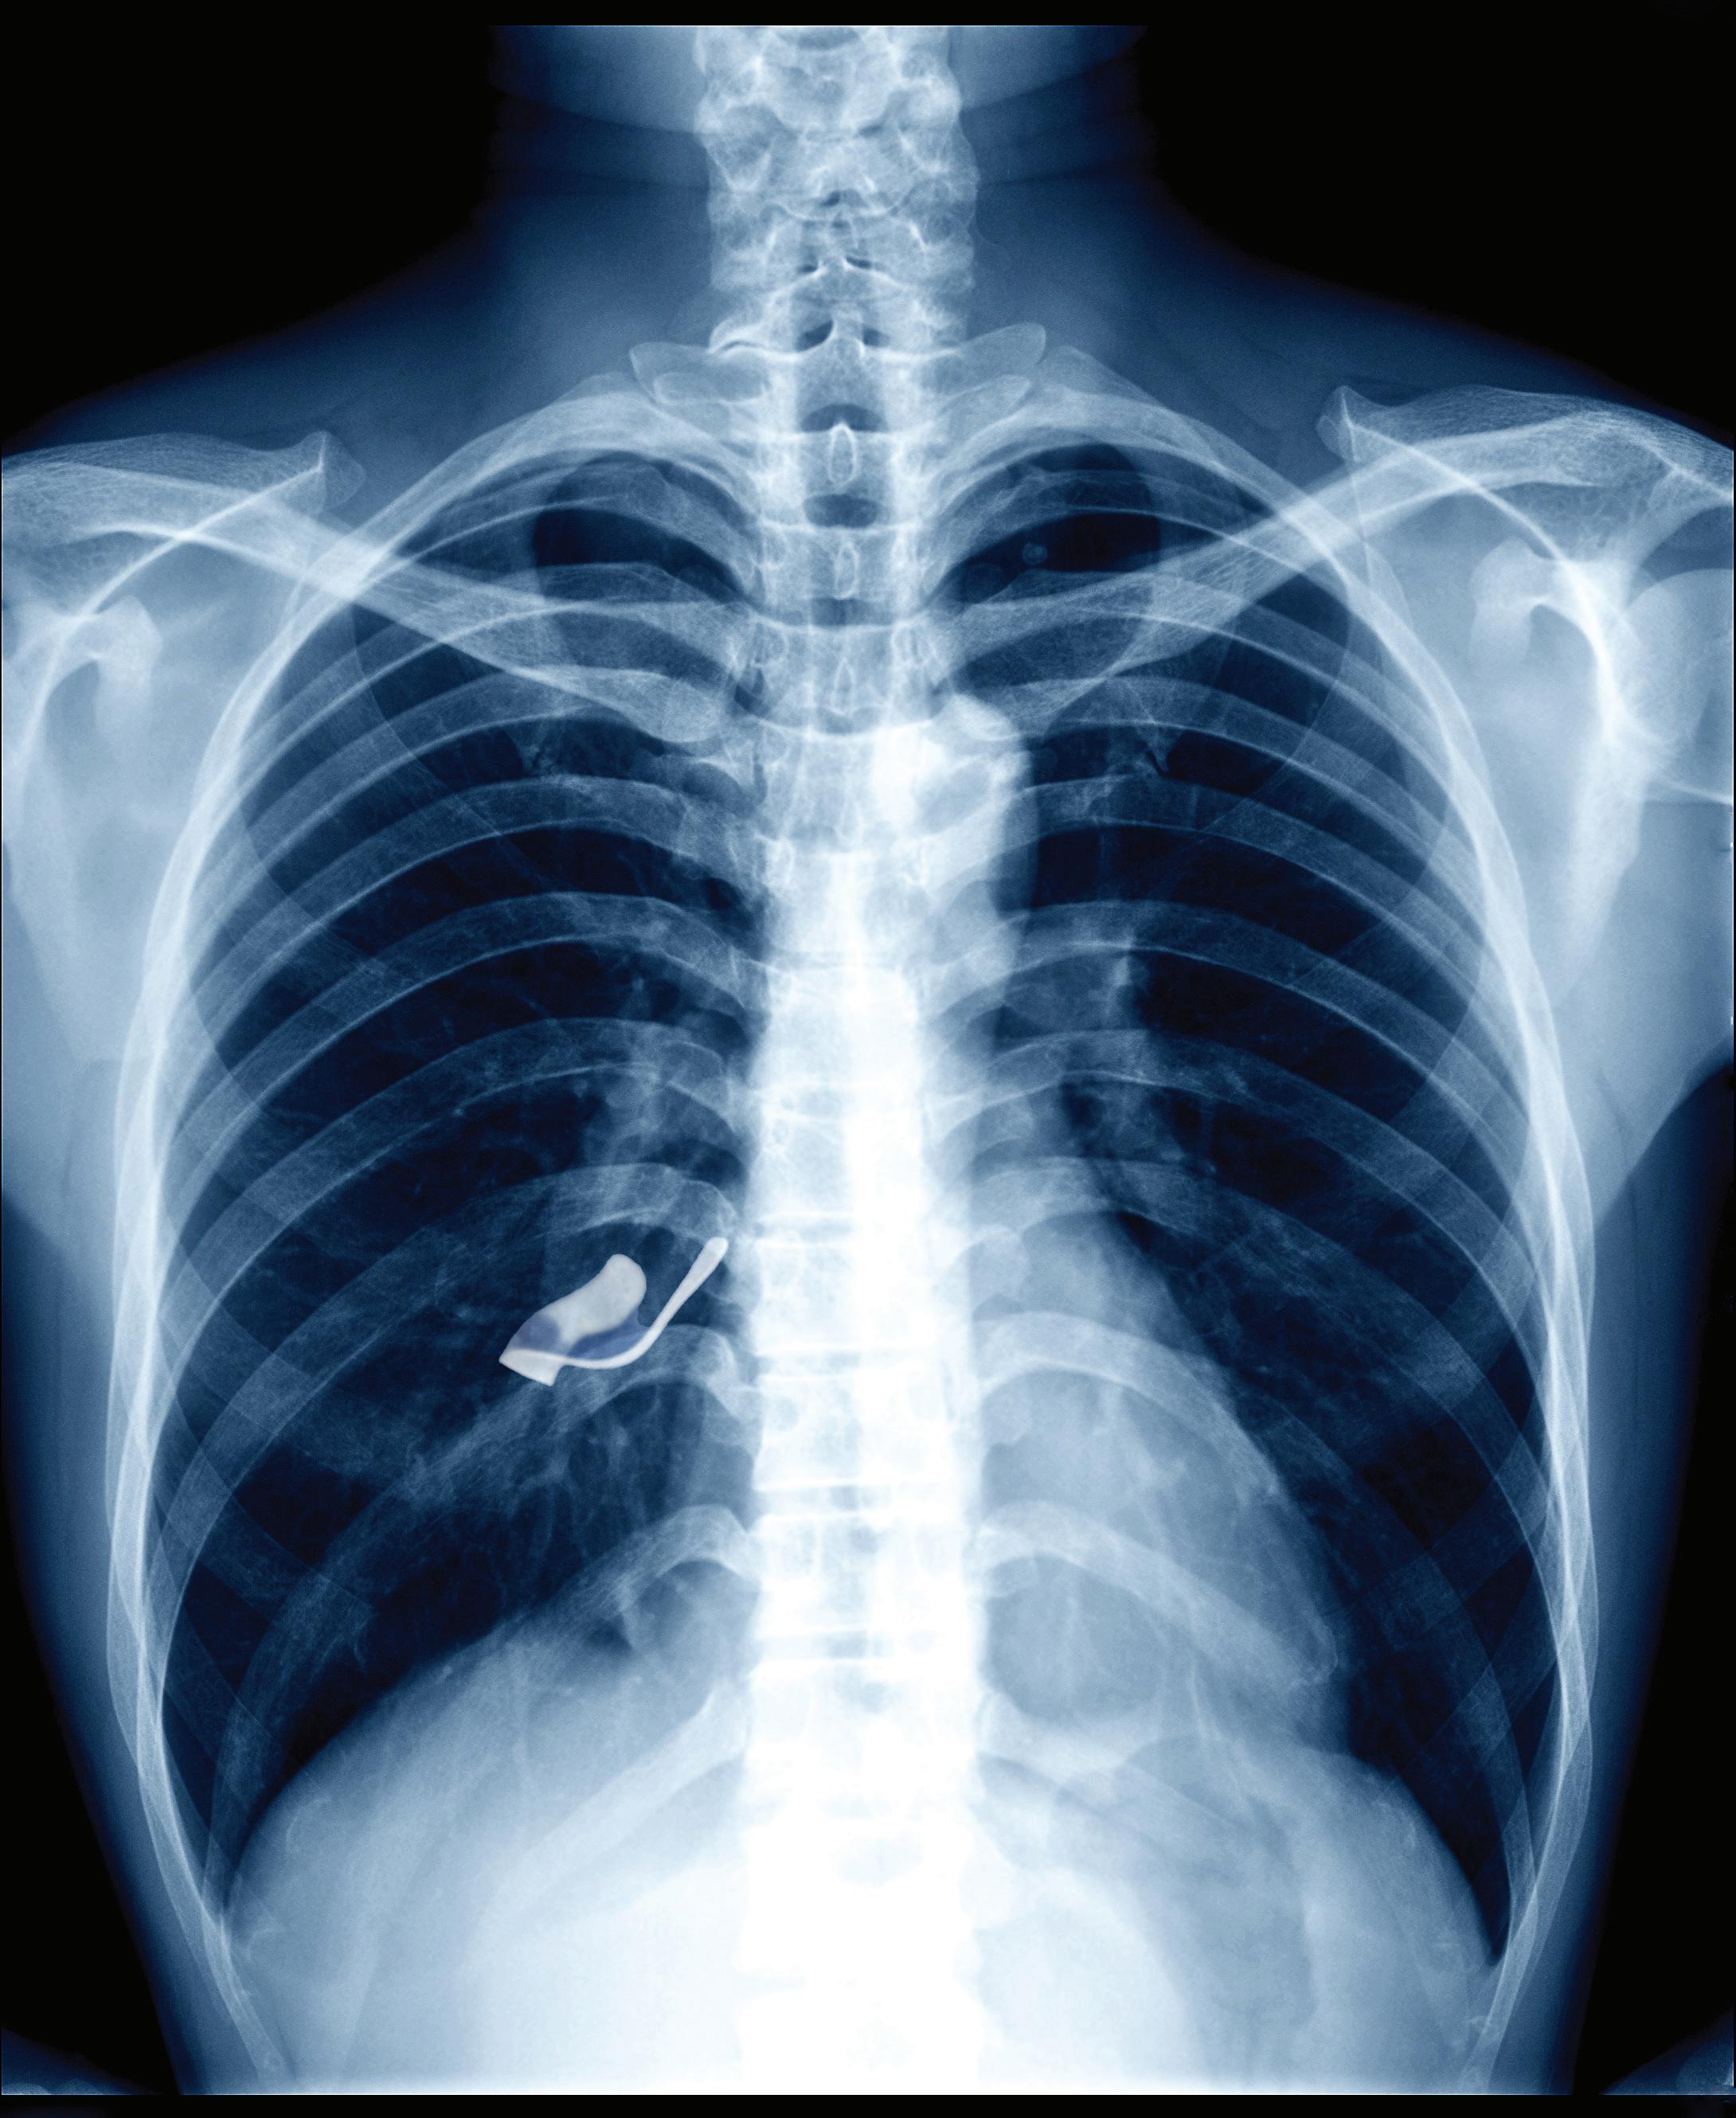

11 days after appendectomy, tests for acute abdominal pain revealed a

retained object

left inside the patient.

Surgical miscounts are considered never events because they are usually preventable by following established procedures.

ProAssurance offers risk assessments designed to help practices minimize errors by establishing and evaluating safety procedures and communication protocols.

With reliable procedures in place, our insureds are more likely to reduce errors in their medical practice, avoid claims, and make claims more defensible if they do occur.